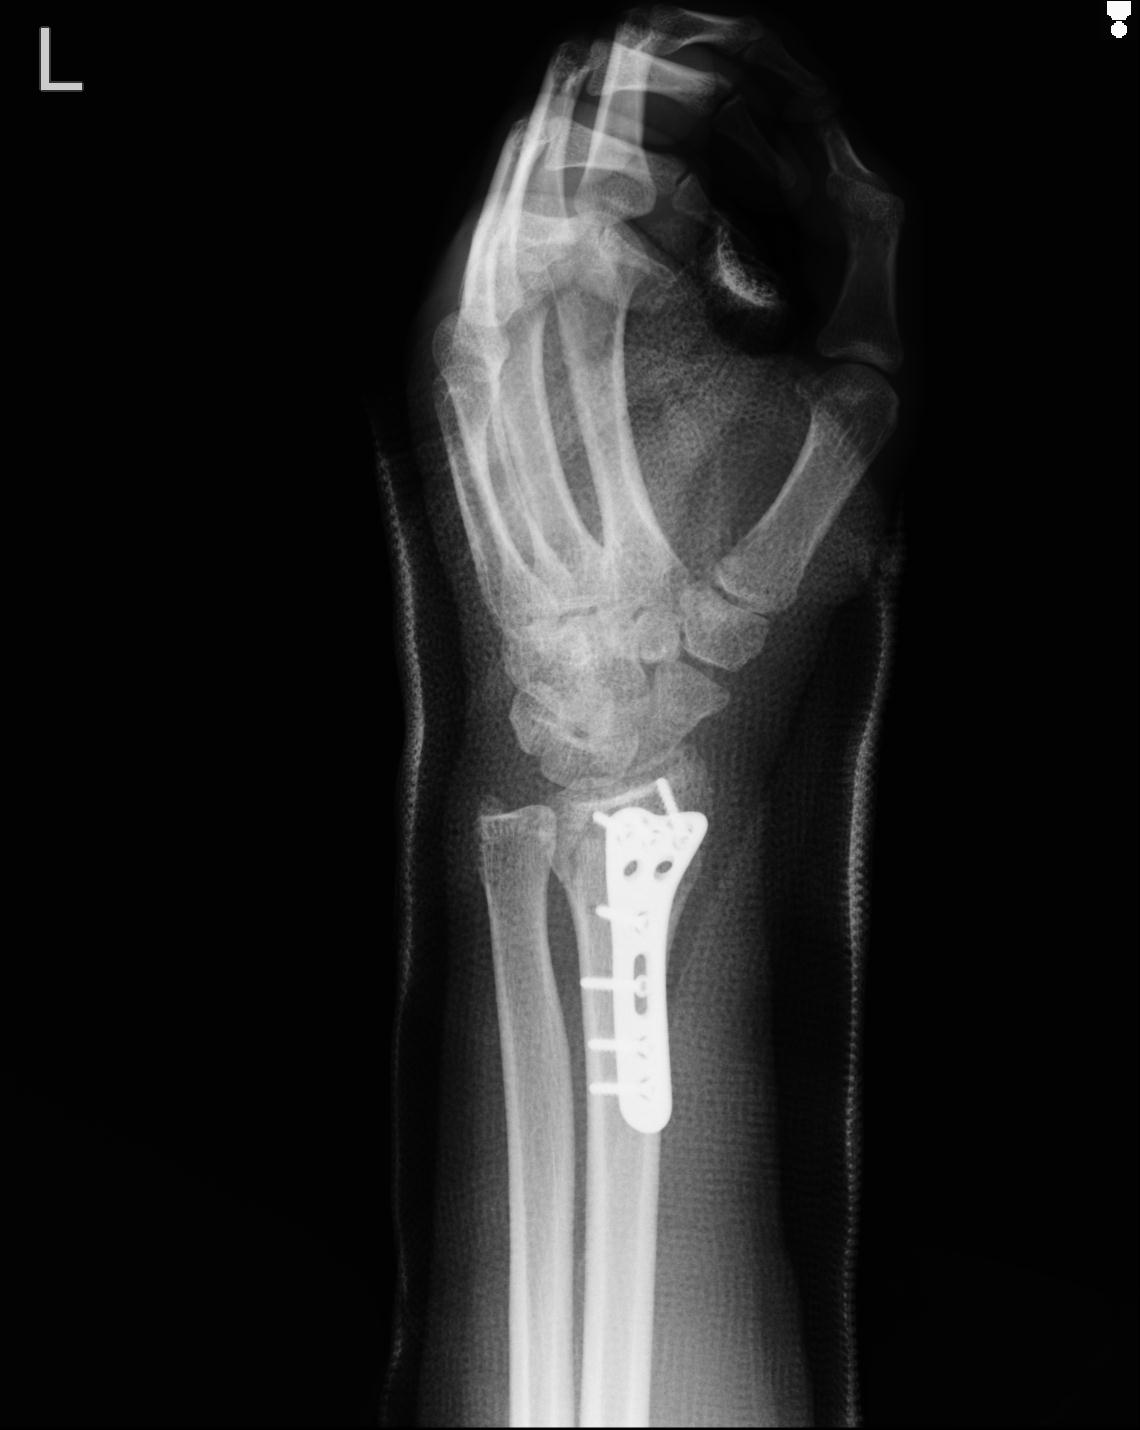

46666 1/23 両股正面+軸と右手関節 2R 76歳女性 右橈骨遠位端

102739 12/30 1/5 左手関節 4R 92歳女性 橈骨遠位端

101290 1/4 5/21 5/20 手関節 2R 17歳男性 橈骨遠位端